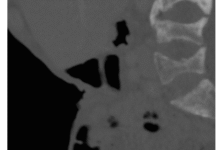

Cervico Facial Actinomycotic Osteomyelitis : A Single Center Experience

Global Journal of Pathology & Laboratory Medicine Volume 2, Issue 1, July, 36-46 Received: April 5, 2023, Reviewed: April 10,…